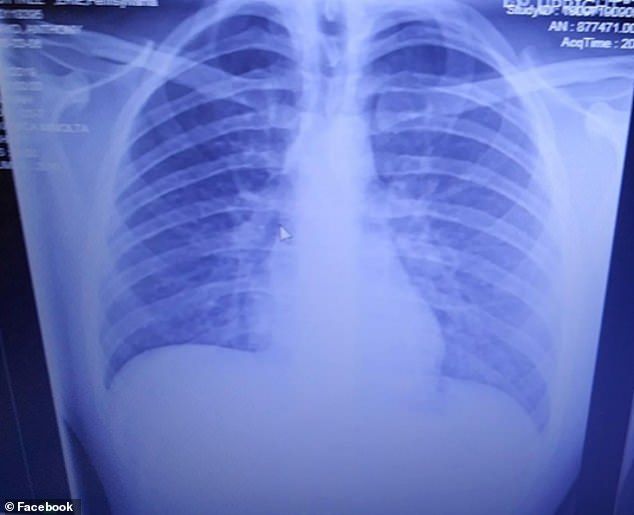

まるで、肺の内側が溶かしたバターで覆わ れてしまったような状態で、類脂質肺炎 (lipoid pneumonia)と呼ばれる特殊な肺炎です 1)。同じグリセリンでも、食べるのと、吸引するのとでは人体への影響がまったく異なり ます。る。プルーム・テックは電子タバコとよく似た構造を い込む。溶液には,ニコチンや果物などの匂いの人工 香料,グリセリン,プロピレングリコールなどが含ま か減らず,十分にリスクが高いと考えられる。また肺 グリセリン単体で吸うことはできるの? 身体に害はあるの? こんな質問に答えます。 本記事ではグリセリン単体で吸う場合に知っておいたほうがよいことを紹介していきます! グリセリン単体で吸えるのか 結論から言えば、吸えます。大体の一般的なvgとpgを混ぜ合わせたeリキッドよ

1日2箱の喫煙者の肺 電子タバコの蒸気を2年間吸い続けた少年 肺に油脂が詰まり60歳のヘビースモーカーと同じになってしまう 米国 すもーるnewsちゃんねる

香り付き電子タバコ歴2年の19歳 肺は ベーコンの油がべっとり付いた状態 米 ニコニコニュース